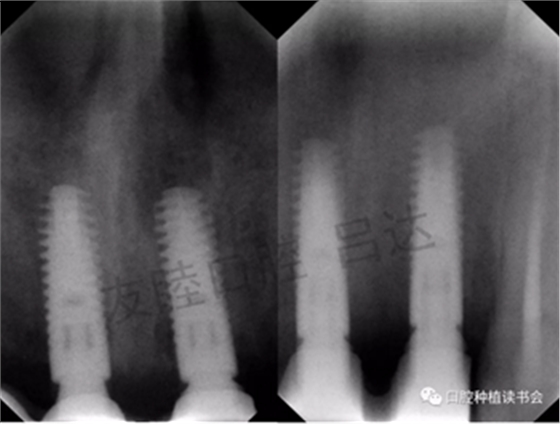

X線檢查:3顆種植體為平臺(tái)轉(zhuǎn)移種植體。冠邊緣與基臺(tái)貼合,骨嵴大致位于種植體肩臺(tái)水平。(圖4)

圖4 種植體X片檢查